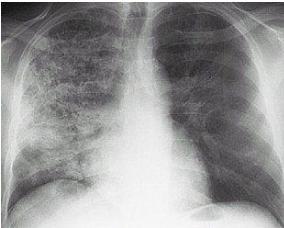

这是最明显的现象,因为很多人都把它当做感冒治了,很容易忽略。小编提醒你,如果服用止咳药一周还是没有效果,您还是去医院做个CT,因为药不对症,肯定不是感冒。还有一种可能,就是患上了肺结核,不过相比较肺癌,它不是大病。之所以建议做CT,不仅是因为他的清晰度高,另个原因是它是分层切割照相的,每一层有变化都是能看出来的。

CT片

千万不要做胸片,因为小编的母亲当时就是做的胸片,当时看时说没事,病情才被耽误的。胸片有个弊端,就是有一叶障目的效果,看不到内部有异常。所以作为子女的而我们,不要怕多花那几百块,毕竟生命只有一次,而且40到50是高发期,需要注意。小编现在还在自责,如果当初我别着母亲去做CT,也不会有这样悔恨。

胸片